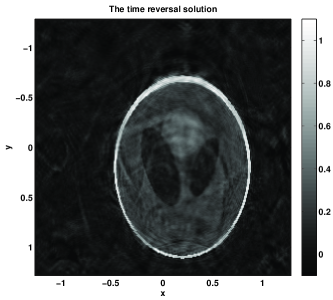

Figure 3: T=2T02.3535𝑇2subscript𝑇02.3535T=2T_{0}\approx 2.3535. The time T𝑇T is slightly above the stability threshold T1/2subscript𝑇12T_{1}/2 but below T1subscript𝑇1T_{1}. The error of the NS solution is 6.63%percent6.636.63\% with k=8𝑘8k=8 (999 terms) of the series vs. error 37.76%percent37.7637.76\% for the TR one. Since T<T1𝑇subscript𝑇1T<T_{1}, the TR solution does not recover the correct size of the jumps — they are recovered with amplitudes ranging from 1/2121/2 to 111, and for many of them, it is just 1/2121/2; this is clear from the slice diagrams. In contrast, the NS solution has the right amplitudes and would improve with more terms.

Figure 3: Example 1 with the non-trapping speed c1subscript𝑐1c_{1}. Case 2: T=4T0𝑇4subscript𝑇0T=4T_{0}. (a): the boundary distance map. (b): the exact initial condition. (c): the time reversal solution. (d): the Neumann series solution. (e): x𝑥x-slices of the time reversal solution (continuous line) and the exact solution (a dashed line). (f): x𝑥x-slices of the Neumann series solution (continuous line) and the exact solution (a dashed line). (g): y𝑦y-slices of the time reversal solution (continuous line) and the exact solution (a dashed line). (h): y𝑦y-slices of the Neumann series solution (continuous line) and the exact solution (a dashed line).